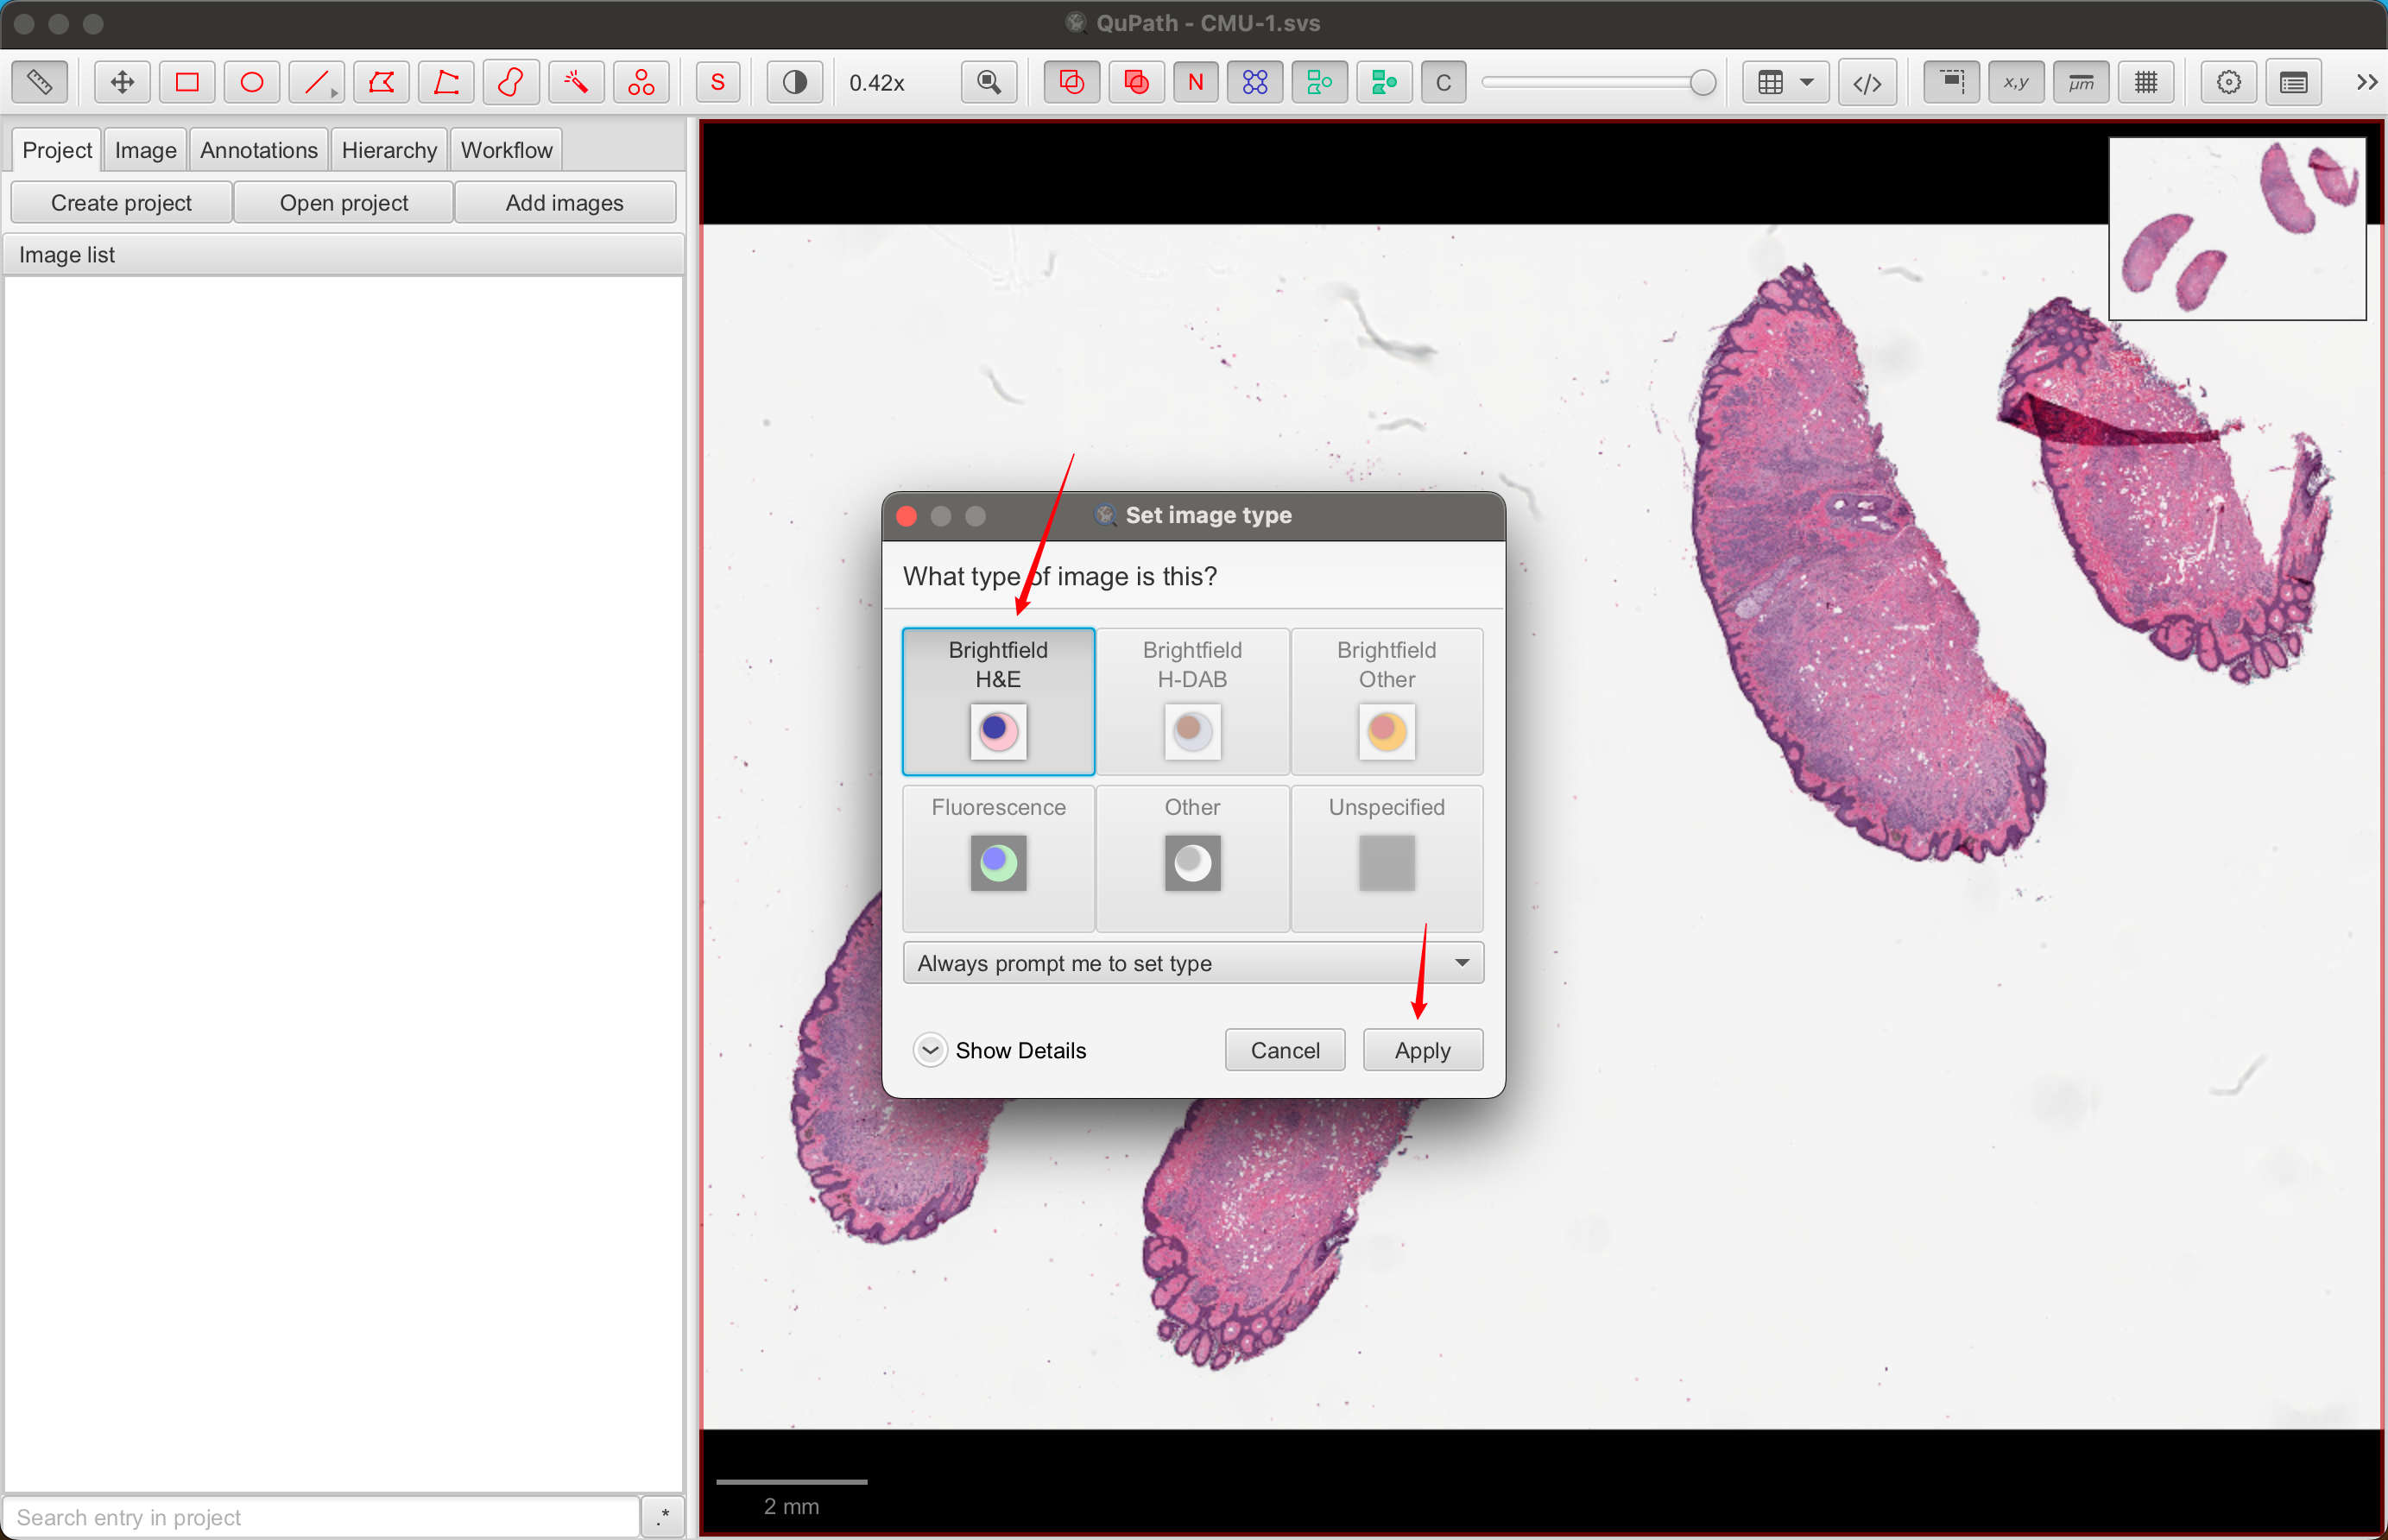

1-3:查看图像属性

通常,QuPath 窗口左侧有一个面板:分析面板。如果没有,请单击工具栏上的分析面板按钮将其打开。

这里有几个选项卡,您稍后会遇到。现在,单击**“图像”**选项卡以获取与您的图像相关的属性表。